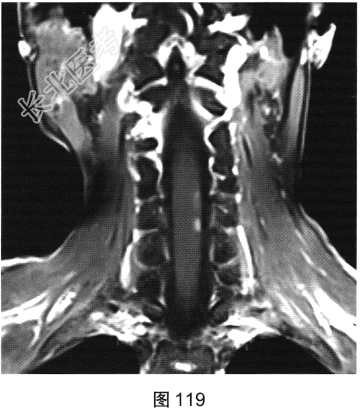

- 多项选择题2.[提示]患者行脊柱MRI检查,如图115~图120所示。患者MRI检查可见哪些阳性影像学表现( )

A、T2WI示颈髓和胸髓病灶呈高信号

B、增强扫描颈髓病灶多发斑片状强化

C、横断面增强扫描脊髓侧索病灶强化

F、T1WI示颈髓病灶呈等信号